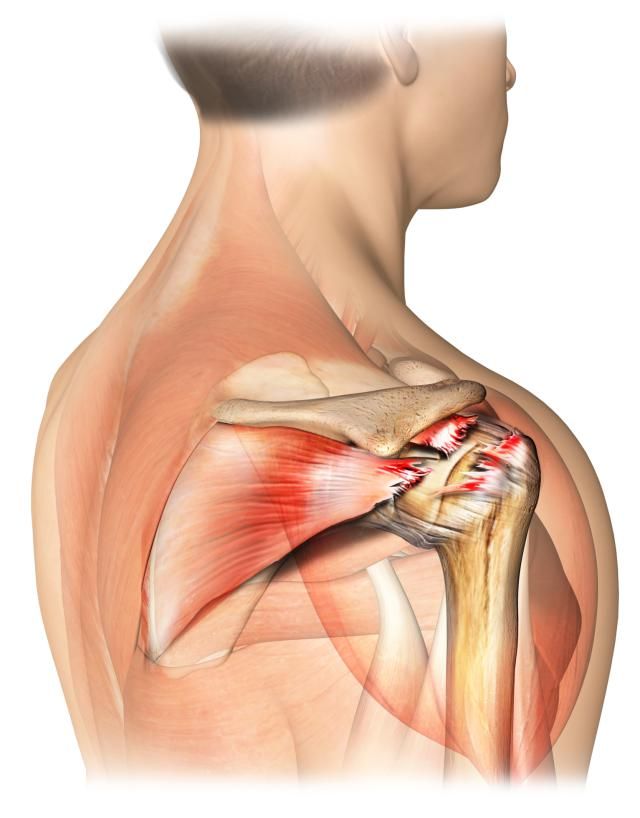

●肩袖损伤:肩袖是一个非常复杂的结构,我们通常也称之为旋转袖,分别由冈上肌,冈下肌,肩胛下肌以及小圆肌的肌腱构成。肩袖对于肩关节的整个活动起到了非常重要的作用,同时还有稳定肩关节的作用。

导致肩袖损伤的原因有很多,比如外伤、比如退化、比如肩关节撞击。

肩袖出现损伤的患者,疼痛比较明显,在夜间的时候可能会出现明显的加重,而且患者有可能出现典型的“疼痛弧”,也就是活动到一定角度的时候疼痛开始出现,但随着角度的加大,疼痛慢慢的减轻了,有一些患者随着病情时间的延长,会出现肩关节的肿胀,出现肩关节的粘连!

诊断:对于肩袖损伤的诊断,首先患者要有相应的症状,要去医院寻求医生的帮助,医生要进行相应的查体之后,根据患者的症状结合自己的查体进行核磁检查,来明确是否存在肩袖损伤的症状、查体以及核磁互相印证的时候就可以做出确定诊断。

治疗:如果疼痛不是特别严重,肩关节粘连不是特别的明显,肩袖不是全层撕裂的话,可以采取保守治疗。可以通过口服或者是外用非甾体抗炎镇痛药帮助患者控制疼痛,可以通过专业医生的手法治疗,放松紧张的肩关节周边的肌肉,对于有粘连的患者可以通过手法治疗进行松解,帮助患者恢复更好的肩关节活动角度。可以采取局部封闭注射的办法,帮助患者控制疼痛和关节内的炎症反应。

但如果是肩袖全层撕裂,患者疼痛比较明显,肩关节的功能严重受限,而且患者有主观意愿,想要解决问题的时候,需要进行肩关节镜手术治疗,对肩袖进行缝合或者是止点重建。